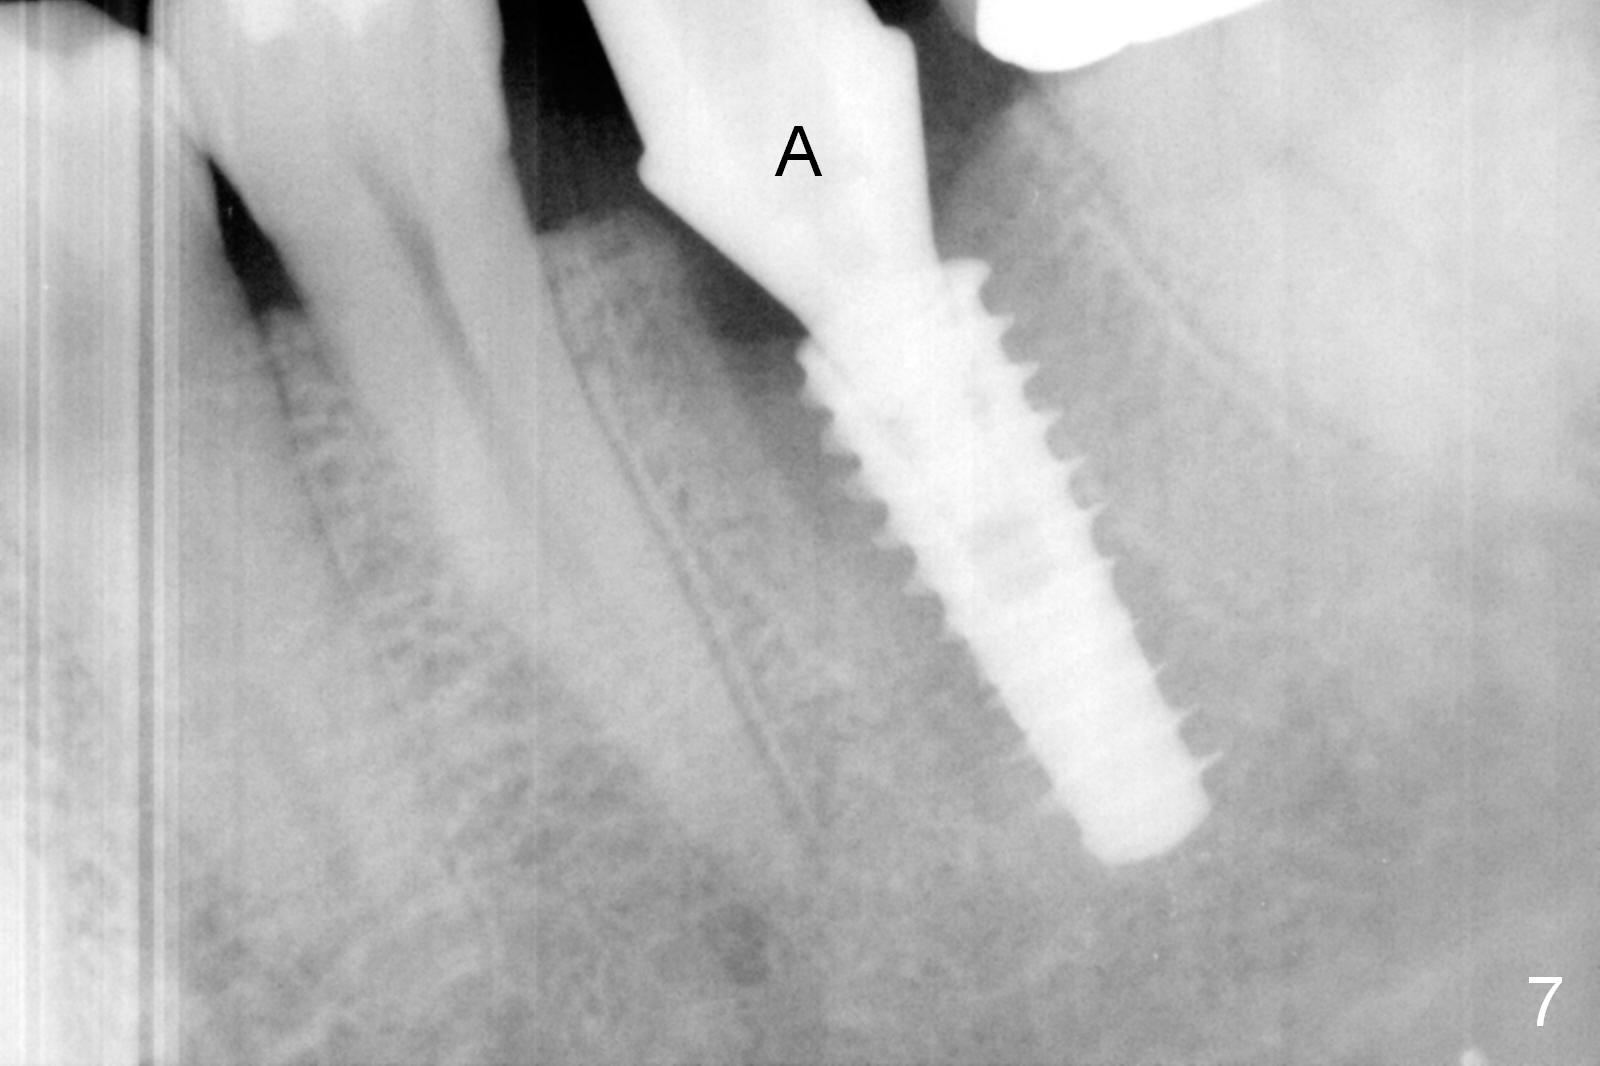

The tooth #19 is easy to get loose, but it cannot be luxated. After sectioning and extraction (Clindamycin), the septum is found to be thin (Fig.4). A surgical fissure bur is used to initiate osteotomy, followed by 1.6 mm pilot drill. It is difficult to use Marking bur (wobbling over the basically pointed septum). It is impossible to use 4.3 mm Magic Drill (MD, one drill system), since it jumps. The smallest MD has to be used (2.8 mm). When the next drill (3.3 mm) is being used for 13 mm with stopper (Fig.5), the patient experiences transient pain. The depth is suggested from the design in Fig.2. The thin septum appears not to be a reliable landmark. When block anesthesia is administered, the initial depth should be shortened. The drill appears to be close to the Inferior Alveolar Canal (Fig.5). Then the depth changes to 11 mm with the following drills (3.8 and 4.3). The mesial and distal walls of the septum are gradually perforated. A 5x9 mm dummy implant is placed only after using 4.8 mm drill (Fig.6). The implant appears to be short. When a longer implant is placed (5x11 mm), it does not easily enter the osteotomy, either sliding into the mesial or distal socket with the implant separating from the implant driver. It appears that a premount implant is appropriate in this situation. When the 5x11 mm implant is finally seated with stability, it is 6 mm apical to the gingival margin. The longest cuff of IBS abutment is 4 mm. A longer implant is needed (Fig.7, 5x13 mm). Placement is not easy as mentioned above. Insertion torque is <20 Ncm when the patient experience a little discomfort. A 6.5x4(4) mm pair abutment is placed (A), apparently proper for restoration. Allograft is placed (Fig.8 *) prior to immediate provisional. The patient complains of bad smell from the site 24 days postop. When the provisional is removed, the abutment is found to be mobile. When the latter is removed with local anesthesia, bone graft granules are attached to the socket above the lightly mobile implant (Fig.9). In fact the latter appears to be stable after a few turns by finger. A healing screw is placed; the socket is closed with collagen plug and 4-0 Chromic gut sutures (Fig.10). It appears that a larger implant should have been used to achieve higher torque. Two months later (3 months postop), the coronal end of the implant is partially exposed. A 5x4 mm healing abutment is placed. It appears that the implant is stable. The implant appears to have osteointegrated 4 months postop (Fig.11). Impression is taken.